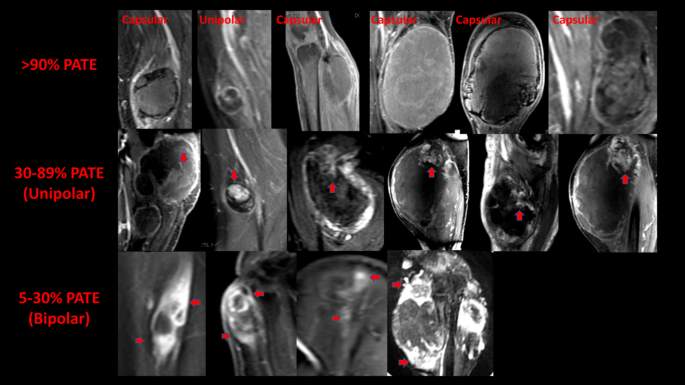

Representative PWI/DCE morphologic patterns from UPS patients at PRT classified by PATE are presented in Fig. 4.

PWI/DCE morphology patterns are classified by pathology-assessed treatment effect (PATE). Representative PWI/DCE morphology patterns from UPS patients with > 90% PATE (top panels), 31–89% PATE (middle panels) showing unipolar enhancement (red arrows), and 5–30% PATE (bottom panels) showing bipolar enhancement (red arrows).

In the responder’s group (n = 14) (R), 79% (n = 11) displayed a “Capsular” pattern (P = 1.49 × 10−7), 14% (n = 2) had a “Unipolar,” and 7% (n = 1) had a “Non-Nodular” pattern (Fig. 5). In the partial responder’s group (n = 10) (PR), 80% (n = 8) displayed a “Unipolar” morphology (P = 1.03 × 10−5), and 20% (n = 2) had a “Bipolar” pattern. In the non-responder’s group (n = 6) (NR), 50% (n = 3) displayed a “Bipolar” pattern (P = 0.1562), 33% (n = 2) a “Semi-Lunar” pattern, and 17% (n = 1) a “Solid-Enhancement” pattern. A significant statistical association was observed between the PRT “Capsular” enhancement pattern and the responder’s group (R) (P = 1.5 × 10−7) and between partial-responders (PR) and the “Unipolar” pattern (P = 1.0 × 10−5) (Fig. 5).

A combination of morphologic, qualitative, and semiquantitative PWI/DCE features has helped differentiate responders from partial/non-responders (Figs. 5, 6 and 7). Our results have shown that a “Capsular” pattern is a typical PWI/DCE morphologic feature in the responder group (P = 1.49 × 10−7). A clinical radiologist can readily recognize this pattern without the need for post-processing software as is required for first- and high-order radiomic feature extraction. However, suboptimal responders tend to display a “Unipolar” or “Bipolar” pattern at PRT. The finding of the described patterns appears to follow a set pattern where “capsular” is the latest pattern of response, following “unipolar” and “bipolar,” respectively. This progression may be partly linked to the presence of an underlying “sarcoma organ model” with a dominant vascular supply at the superior pole, a secondary vascular supply at the inferior pole, and a likely arterial perfusion gradient from superior to inferior and from peripheral to central/equatorial, as illustrated in Fig. 12.